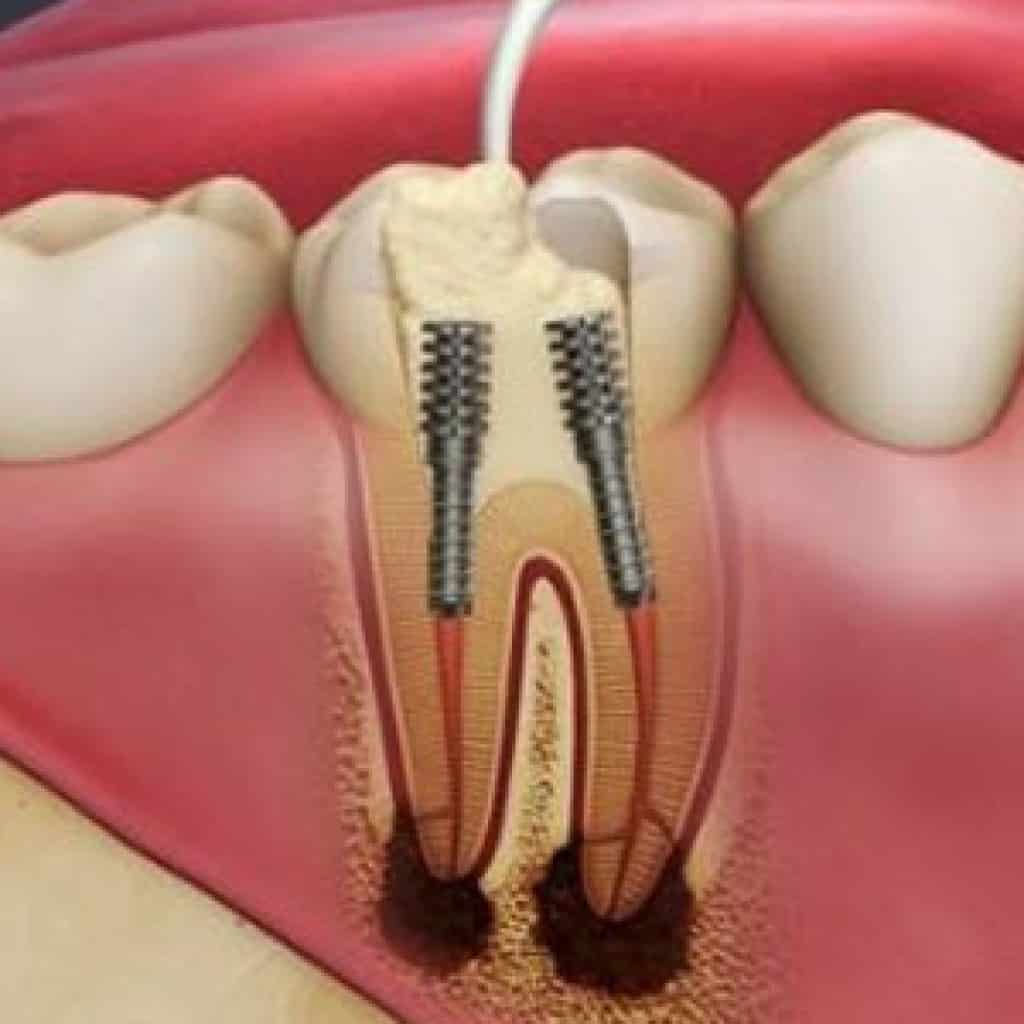

محفظة داخل دندان که حاوی رگهای خونی و عصب ها است پالپ نام دارد. خوردن بیش از حد در عارضه پرخوری عصبی باعث افزایش پوسیدگی دندان ها می شود اسیدهای قوی که در اثر استفراغ کردن از دهان خارج می شوند می توانند دندان ها را ضعیف و شکننده کنند این اسیدها همچنین باعث بوی بد دهان می. کشیدن دندان شیری رویش دندان شیری ریزش دندان شیری خراب شدن دندان شیری ریختن دندان شیری دندان شیری تعداد دندان شیری دندان شیری کودکان. من سی سالمه و اکثر دندان هام خراب شده یکی رو کشیدم دو تا رو پر کردم و دو تای دیگه رو هم دکتر گفت باید پر کنم و نیاز به عصب کشی دارند.

مهم ترین کار یک معاینه ی کامل است این معاینه شامل نگاه سطحی بر دندان های شما گرفتن عکس با استفاده از اشعه x از آنها و ساختن مدل پلاستیکی از دندانهای شما میشود سپس تیم دندانپزشکی یا. عکس بیت کوین به زودی وارد مبادلات مالی می شود. تشخیص پوسیدگی دندان ها از روی عکس های رادیو گرافی کاری است که نیاز به علم مربوطه دارد.